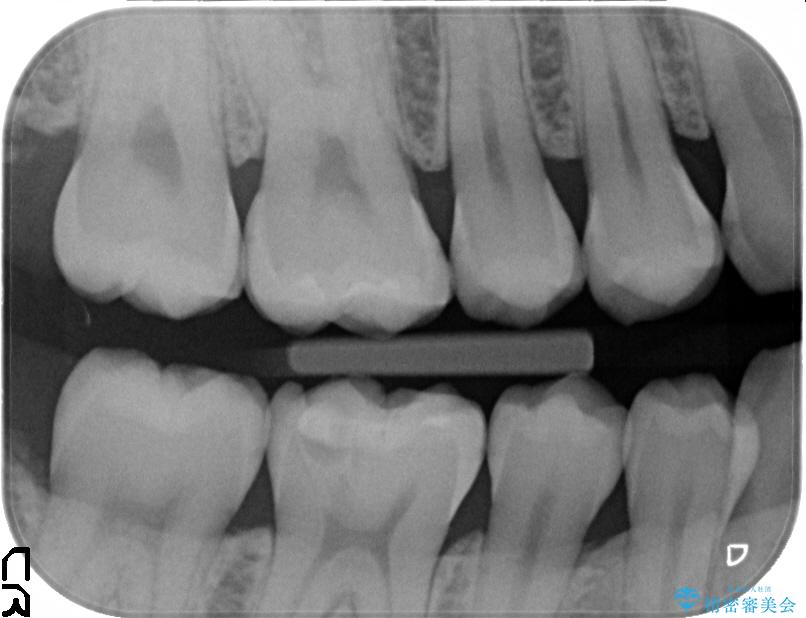

診査をした結果、顎左右の前から6番目の歯に深い虫歯があったため、詰め物(インレー)タイプで修復していく(e-max プレスインレー)での治療を行いました。

今回は歯の黒ずみを気にしてご来院されましたが、診査をしますと神経の治療が必要になる一歩手前の状態である神経の近くまで虫歯が広がっていました。

無症状で静かに進行している虫歯

「虫歯=歯が痛い」というイメージがありますが、実際には時間をかけ少しずつ静かに虫歯は進行しています。

無症状でも歯の奥深くまで進行していることが多くあり、できるだけ早めの治療をおすすめいたします。